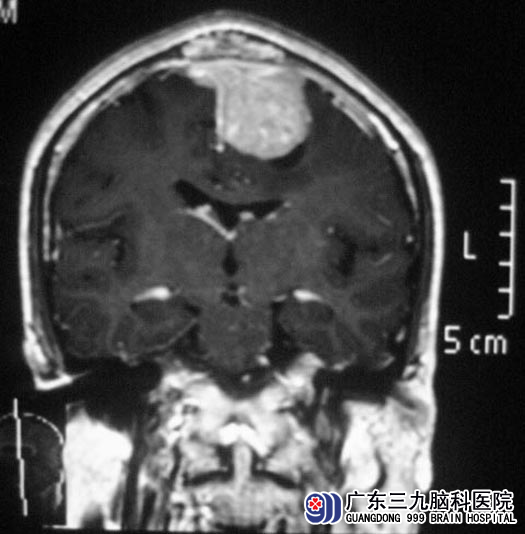

在医院检查发现这不是简单的头皮包块,CT检查提示:“左侧额部大脑镰旁巨大占位”。广东三九脑科医院进一步MRI检查:左侧额部镰旁脑膜瘤,大小约34.5mm×45.1mm×38.4mm,并侵蚀病变区邻近颅骨;MRV检查提示:上矢状窦前段闭塞,并有透明隔腔形成。http://www.999brain.com/

肿瘤已破坏正常颅骨,由颅内生长至颅外,使瘤体,颅骨和头皮组织生长在一起,已经失去了正常的解剖层次,无法正常分离,如稍有不慎就会造成术中大出血、损伤正常脑组织、遗留术后肢体瘫痪等并发症,甚至危及生命,手术风险大,技术难度高。http://www.999brain.com/

▲手术前